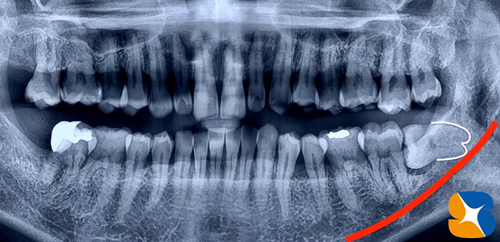

京都出身のタレント女性。主訴は「親知らず辺りに虫歯似の痛みがある。仕事柄、休みが取れないので入院して抜歯なんて出来ない。友達のお母さんの紹介で知った。先ずは手持ちのレントゲンを送りますので、お返事を下さい。」とのことでメールを受ける。

当院でのCT画像チェック。

歯根はかなり湾曲しているが、「抜歯の際に力のさじ加減さえ上手くコントロールすれば、歯根の先を折ることもなく、短時間で抜歯が可能」との判断で、初診時での抜歯に試みました。

予測通りの抜歯が終わり、止血と術後の腫れを抑える目的で血液を採血して院内製作したコラーゲンを歯を抜いた凹穴に充填して終了となりました。